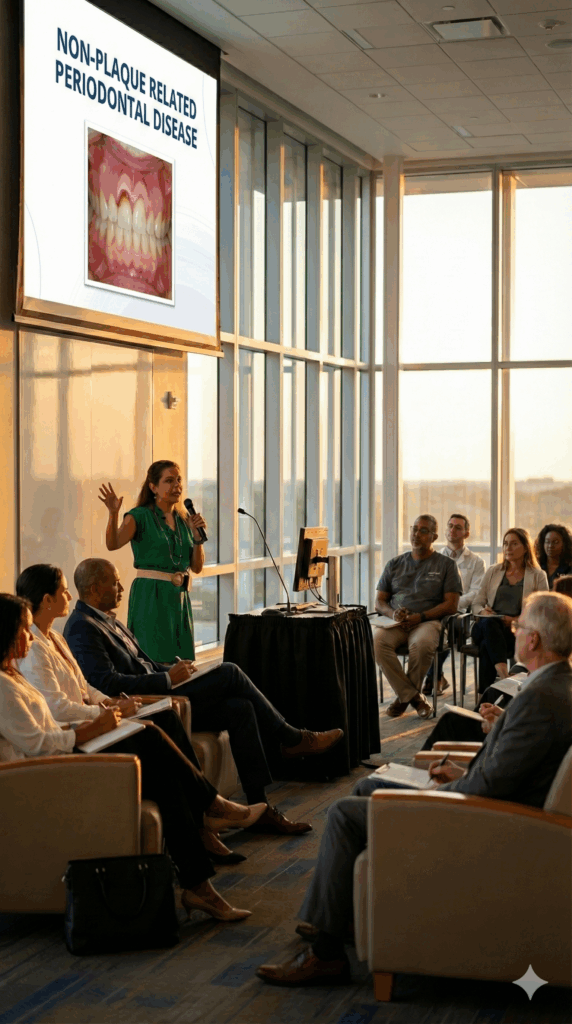

Keynote Speaking

Where clinical insight meets storytelling. These keynotes bring oral pathology to life through powerful visuals, relatable cases, and clear diagnostic takeaways. Ideal for conferences, CE events, professional associations, and academic programs seeking inspiring, evidence-based content delivered with clarity and intention.